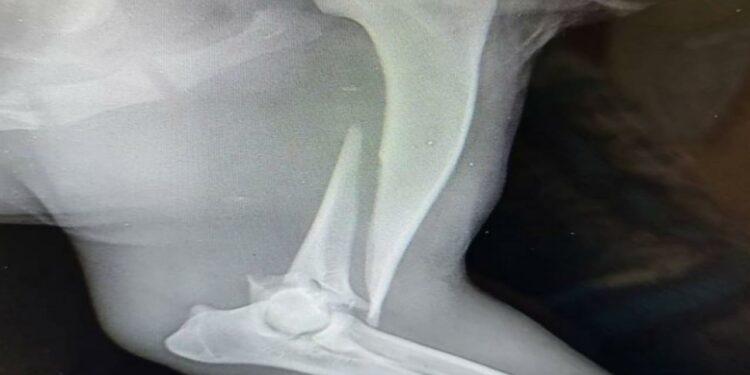

«Нам сообщили, что ее сбила машина. Мы долго искали ее и нашли. "Хатико" сбила машина, у него сломана лапа. Сейчас он находится у нас. Минимум месяц потребуется для восстановления. Это при условии, что мы сейчас найдем хирурга. Ему требуется операция. По стоимости пока ничего не можем сказать. Но примерно от 50 до 100 тысяч тенге потребуется на операцию», - говорит руководитель Центра реабилитации раненых бездомных животных при Общественном фонде «Сердца Павлодара» Мария Гребенкина.

Фото со страницы Центра реабилитации раненых бездомных животных в Instagram